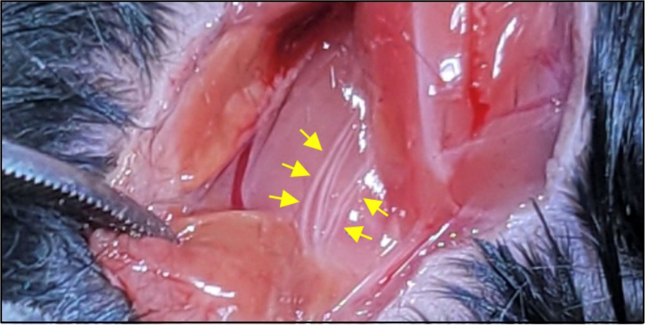

뇌혈관장애 및 퇴행성뇌질환 개선연구

- 연구주제 : 뇌경색 동물모델 구축을 통한 뇌혈관 장애 및 염증제어 후보물질 발굴